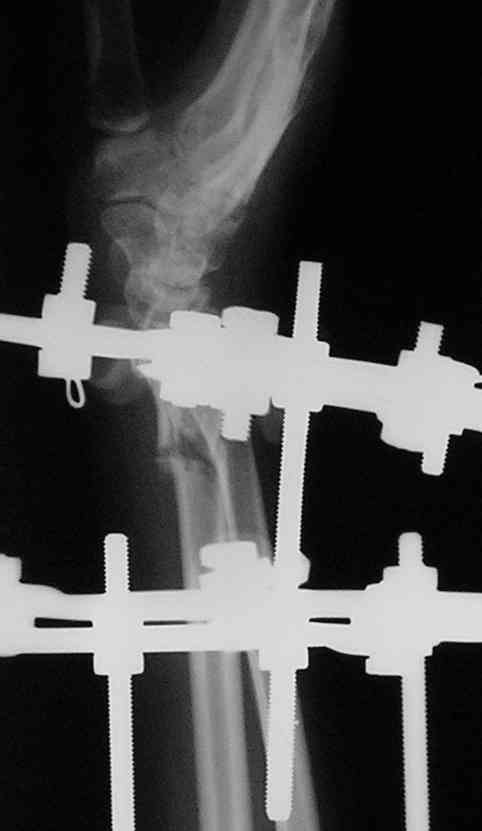

У больного/ой кроме перелома лучевой кости и шиловидного отростка локтевой, разрыв дистального радиоульнарного сочленения, перелом ладьевидной кости и ладьевидно-полулунная диссоциация.

Если позволите свое мнение, не стал бы лечить аппаратом эту травму, перелом луча не консолидировался: открытая репозиция+ костная пластика+ пластина, синтез ладьевидной кости, по возможности шов ладьевидно полулунной связки,

если восстановить связку не представляется возможным, фиксация 2 спицами.

Судя по показанным Рг граммам, очевиден посттравм. артроз лучезапястного сустава, проблема дистального радиоульнарного сочленения(TFCC).

Угол наклона лучевой фасетки в норме в пределах 10-15 градусов, на представленном боковом снимке -может быть чуть больше 15градусов. Выполнив

разгибательную остеотомию луча, ты поставишь фасетку в нейтральное положение и таким образом увеличится угол разгибания , но уменьшится сгибание. По сути, амплитуда движений останется такой же.